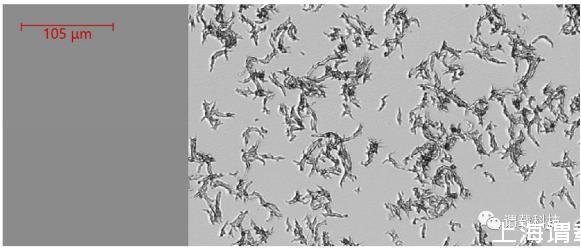

圖3、Biosense微生物動態監測系統捕獲的7h30分鐘時刻對應的膿腫分枝桿菌(粗略表型)生長延時圖(典型蛇形索成像)